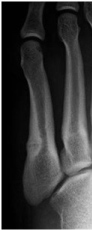

Patient 1: 20-year-old female, long jump athlete

In June 2015, pain around the fifth metatarsal gradually worsened, preventing the patient from training. The patient was diagnosed with a stress fracture of the fifth metatarsal at another hospital and conservative therapy was chosen because the fracture line was restricted to the cortical bone (Figure 2a). However, bone union had not been achieved at 3 months after the original injury, so the patient attended a consultation at our hospital. The patient was treated with two rounds of ESWT over a period of 4 weeks and bone union was achieved at 9 weeks after the first round of treatment (Figure 2b). The patient returned to competition after 12 weeks (Figure 2c).

Figure 2A: X-ray at the time of injury in Patient 1. View Figure 2A

Figure 2B: X-ray at the time of pre ESWT in Patient 1. View Figure 2B

Figure 2C: X-ray at 12 weeks after ESWT in Patient 1. View Figure 2c